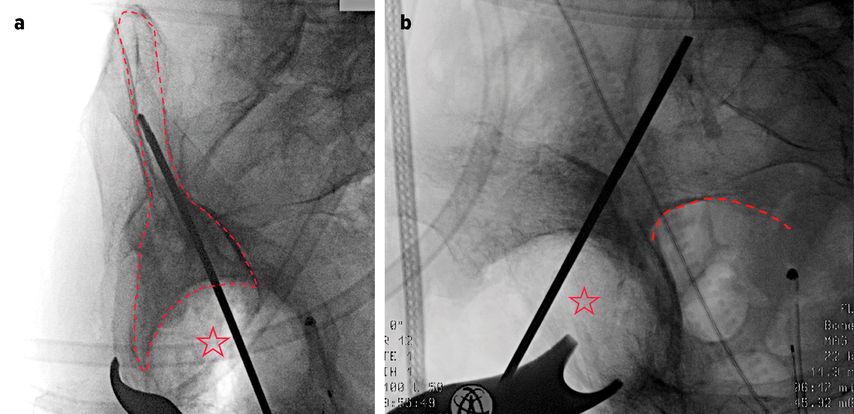

Implantation der PRS-Rekonstruktionspfanne

Die PRS-Pfanne zeichnet sich durch ihre massive Bauweise, multiple Schraubenoptionen und die Möglichkeit einer zentralen Ileumschraube aus. Nach Einbringen der Pfanne wird diese korrekt ausgerichtet (Inklination ca. 40–45°, Anteversion ca. 15–20°). Der entscheidende Schritt ist die Platzierung der zentralen Ileumschraube. Dafür wird unter Bildwandlerkontrolle ein Bohrdraht in den supraazetabulären Korridor gesetzt (Abb. 3a u. 3b) und mit dem 6-mm-Bohrer überbohrt. Anschließend wird die Schraube durch das entsprechende Positionsloch der Pfanne in den supraazetabulären Anteil des Iliums eingebracht. Dabei ist auf eine ausreichende Schraubenlänge zu achten, um eine stabile Verankerung zu erzielen. Die zentrale Schraube übernimmt eine lasttragende Funktion und wirkt wie eine intrapelvine Abstützung. Zusätzlich wird die Pfanne mit Schrauben im Sitzbein und/oder dem Schambeinast fixiert (Abb. 4). Die PRS-Pfanne erlaubt hierbei eine flexible Schraubenplatzierung, was insbesondere bei komplexen Frakturmorphologien von Vorteil ist.

Abb. 3a und 3b: a) Positionskontrolle des Führungsdrahtes im supraazetabulären Korridor (gestrichelte Linie) in der Obturator-Aufnahme (Stern: Acetabulum); b) Positionskontrolle des Führungsdrahtes in der Ala-Aufnahme (gestrichelte Linie: Incisura ischiadica major; Stern: Acetabulum)